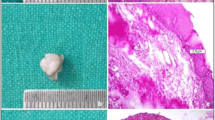

(1) epithelial changes in proximity of the resection margin, evaluated from the edge of the margin to a depth of 1,000 µm. Variables evaluated include nuclear changes, (presence of picnotic, spindle-shaped and hyperchromic nuclei), cytoplasmatic and cell membrane changes (hyperchromic cytoplasm, cell fusion and/or loss of normal cell adhesion), possible intraepithelial or subepithelial loss of attachment on the basis of a cut-off value of 10% of altered tissue in the whole resection margin (Fig. 1); (2) connective tissue modifications, evaluated from the edge of the margins to a depth of 1,000 µm. Variables evaluated included carbonization (thermal necrosis), desiccation (presence of dense eosinophilic layer underlying the possible carbonization area and mainly consisting of collagen denaturation and tissue hyalinization) (Figs. 2, 3, 4); (3) presence or absence of vascular modifications, analyzed by considering a cut-off value of 10% of the above-mentioned changes in the observed area (from the edge of the margin to a depth of 1,000 µm), presence of thrombosed or collapsed blood and lymphatic vessels (including presence of intraluminal clotted erythrocytes, presence of vascular stasis (not-collapsed vessels associated to the presence of gathered erythrocytes); (4) incision morphology, subclassified into regular (presence of a linear, smooth edge for more than 90% of the whole resection margin) and irregular (presence of a rough, uneven edge for more than 90% of the whole resection margin) (Fig. 5). An overall quality score (ranging 0–4) was assigned to each incision, score “4” representing the highest quality.; (5) overall width of tissue modifications, defined as the width of tissue injuries (expressed in micrometers and separately evaluated for the epithelium, fibrous tissue and vascular structures), taking into account the minimum damage width from the resection margin. The area with the most evident damage, perpendicular to the cut margin, was chosen for the evaluation. Changes grossly exceeding the average width of the damage and presumptively associated to manipulation artifacts, were excluded from the evaluation.

Epithelial modifications extending to a depth of ca. 350 μm. (Nd:YAG laser output power 5 W; frequency 30 Hz; fiber diameter 320 µm): nuclear changes, (presence of picnotic, spindle-shaped, and hyperchromic nuclei), cytoplasmatic and cell membrane changes (original magnification: 20×; H&E stained section)

Changes in the connective tissue extending to a depth of ca. 500 μm. (Nd:YAG laser-output power 5 W; frequency 30 Hz; fiber diameter 320 µm): carbonization, presence of dense eosinophilic layer underlying the carbonization area (collagen denaturation) and presence of vascular modifications. (original magnification: 4X; H&E stained section)

Higher magnification of Fig. 2 (magnification: 20×). Presence of collapsed blood and lymphatic vessels and presence of intraluminal clotted erythrocytes